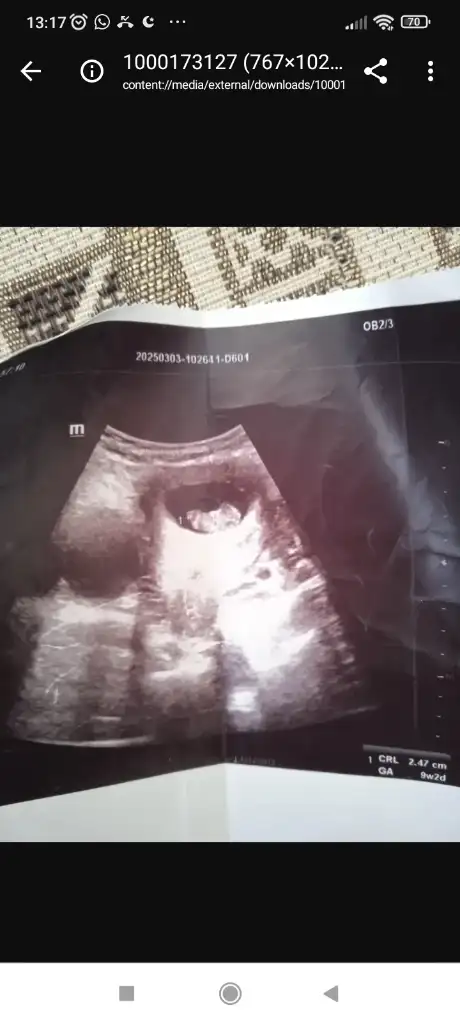

Bizede bakarmısınız lütfenSağlıkla gelsin prenses, hayırlı doğumlar

Kız bebekBizede bakarmısınız lütfen

Kız bebekBize de bakın lütfennnnn.

Teşekkür ederim yorumunuz için sevinmedim desem yalan olur. Neye göre yorumladınız acaba hiç anlamadığım için merak ettim.Kız bebek

Peki burda anlarmısınızKız bebek

Kese yuvarlaksa kiz şekilliyse erkek bebek diyorlar sanırım ona dayanarak tahmin yapılıyorTeşekkür ederim yorumunuz için sevinmedim desem yalan olur. Neye göre yorumladınız acaba hiç anlamadığım için merak ettim.

Burda kafa şekli erkek bebek belli olmuştur artık 14 haftalıkPeki burda anlarmısınız

Yok yaa kız diyorum benBurda kafa şekli erkek bebek belli olmuştur artık 14 haftalıksiz söyleyin

Kesedeki konumuna göre ama oda çok yanıltıyor artıkTeşekkür ederim yorumunuz için sevinmedim desem yalan olur. Neye göre yorumladınız acaba hiç anlamadığım için merak ettim.